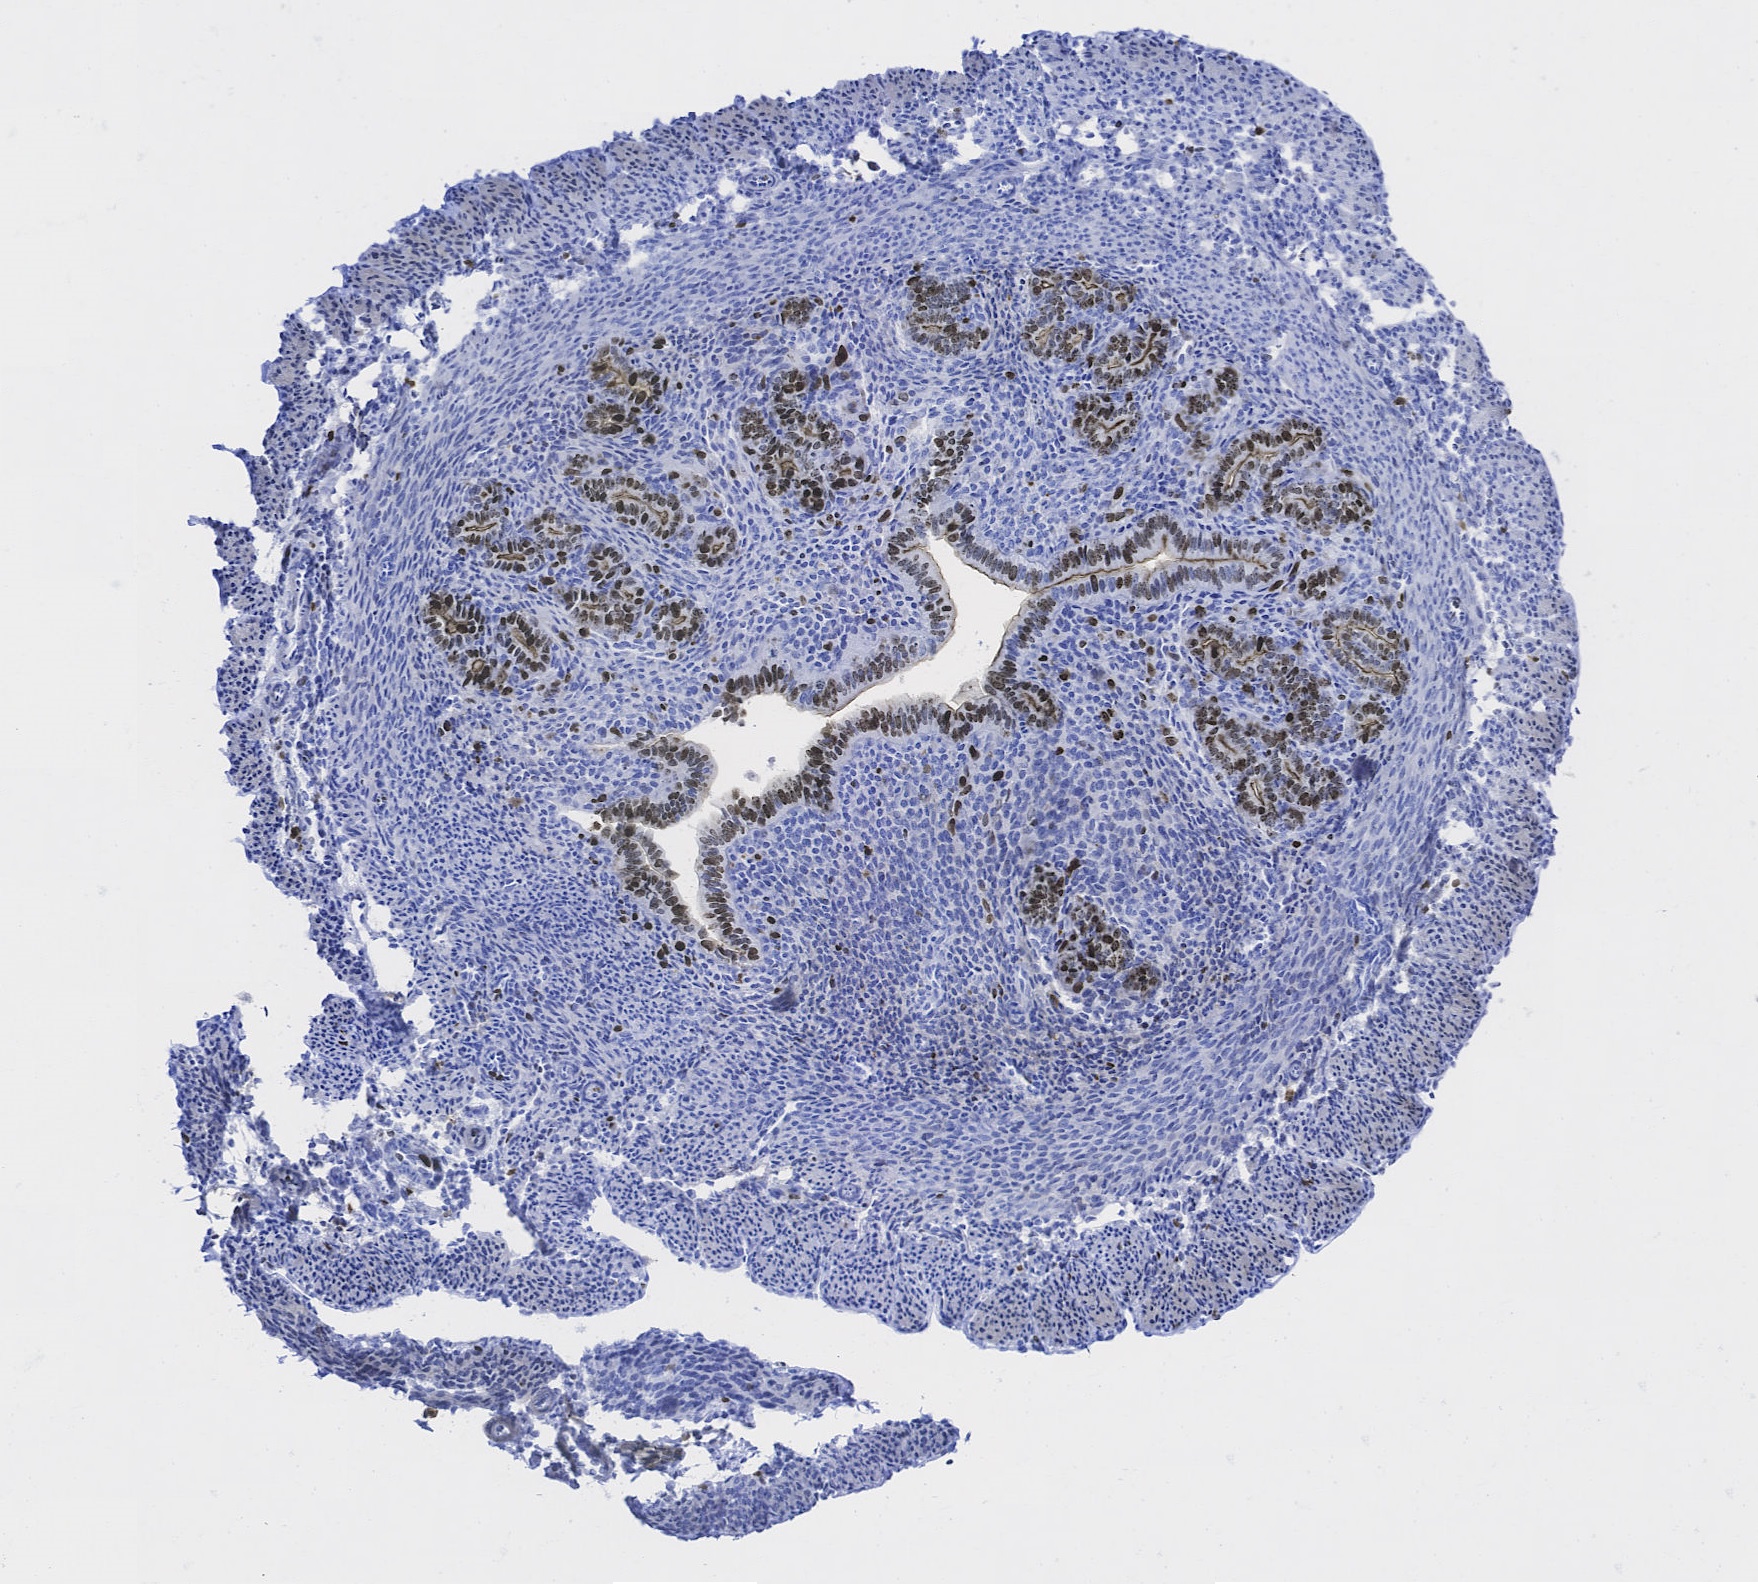

“The tissue is from a mouse uterus that was stained with a Ki-67 antibody. Ki-67 is a nuclear antigen that is expressed in cells that are in G1, S, G2, and mitosis, but not G0 marking the process of cell proliferation.”

Author: Adriana Andrus - Romana Nowak Lab